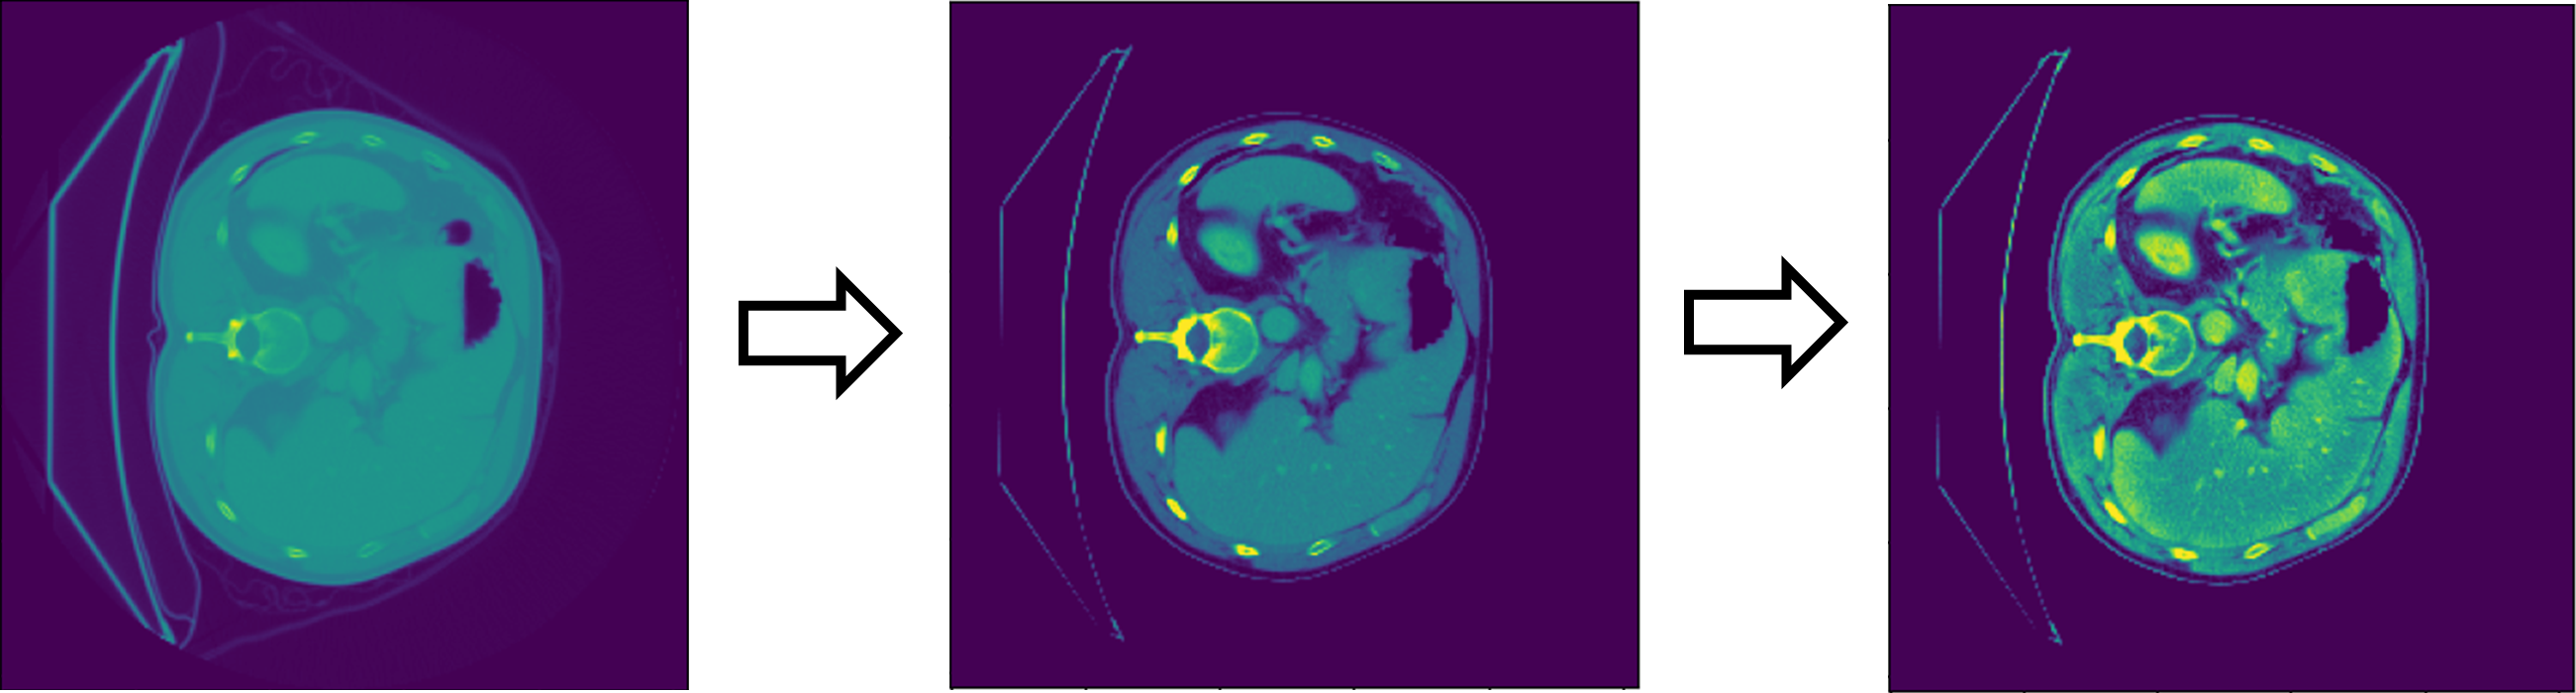

This section outlines the datasets employed, image preprocessing methods, the neural network architecture, the training setup, evaluation criteria, and the processes for 3D modeling and printing. The system addresses liver tissue segmentation by initially processing the CT scans through a ConvNet dedicated to liver segmentation. The resulting masks are applied to the original CT scans to isolate the liver voxels and eliminate extraneous tissue. Subsequently, these refined slices are input into separate ConvNets designed for tumor and vessel detection, which operate concurrently to produce specific tissue masks. Finally, the combined outputs from all ConvNets are merged and transformed into a 3D model of the liver, ready for visualization or printing. Figure 2 succinctly illustrates this workflow.

Upon identifying the optimal liver segmentation model, the approach extends to address segmentation of tumors and vessels. Notably, segmenting the liver first is beneficial for refining the focus of the subsequent tumor and vessel ConvNets. This preprocessing step involves the elimination of background voxels, enhancing the focus on the liver’s critical regions, as illustrated in Figure 2. An example of this process is demonstrated in Figure 10, where an element-wise multiplication is performed between a CT scan slice (record #369, slice 128) and its corresponding ground-truth mask to produce segmented slices that serve as input for subsequent ConvNets.

Following the initial liver segmentation by the first ConvNet, the subsequent tumor and vessel ConvNets utilize the segmented liver output as a mask. This approach helps focus analysis on liver voxels and effectively ignores non-liver voxels, treating them as background. To assess the impact of this method, Table 4 presents comparative results before and after the application of the liver mask in tumor and vessel segmentation tasks. In this evaluation, the OneCycleLR scheduler is employed, as it has shown superior performance over the ReduceLRonPlateau scheduler in these specific segmentation challenges.